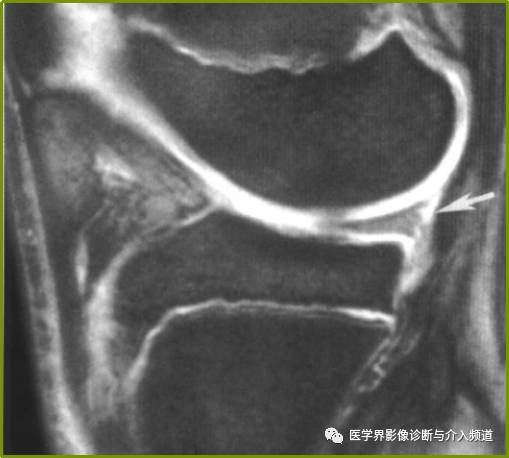

白色箭头所标记为膝横韧带

白色箭头所指为横韧带,黑色箭头所指为内侧半月板前角,位于横韧带正后方

白色箭头所指为横韧带,外侧半月板前角位于横韧带后方

膝横韧带经常容易被误诊为半月板前角撕裂或损伤,我们需要知道有这根韧带,而且要知道它特殊的解剖位置和半月板的形态是否正常,从而与半月板前角鉴别;